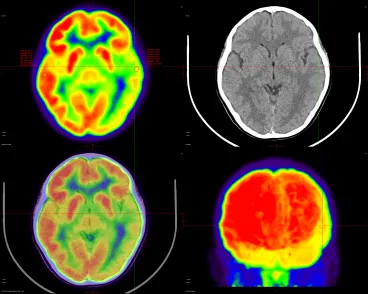

为了明确癫痫病灶,患者家属听从医生建议,带着孩子到前海人寿南宁医院进行PET-CT检查。完成检查后,医院PET-CT结果展示以下表现:

左侧枕叶病灶最明显处SUV最大值为3.939,其放射性摄取与对侧相应部位脑皮质相比降低约25.8%(对侧相应部位SUV最大值为5.106)

左侧颞叶,SUV最大值为3.849,其放射性摄取与对侧相应部位脑皮质相比降低约36.11%(对侧相应部位SUV最大值为5.545)

针对PET-CT呈现的结果,核医学科医生给出了相应的诊断意见:

1.左侧颞叶等FDG代谢明显减低,以左侧颞叶及左下侧颞叶最明显,考虑癫痫灶可能。

2.左侧枕叶等FDG代谢多个局限性放射性摄取明显减低,考虑癫痫灶可能。